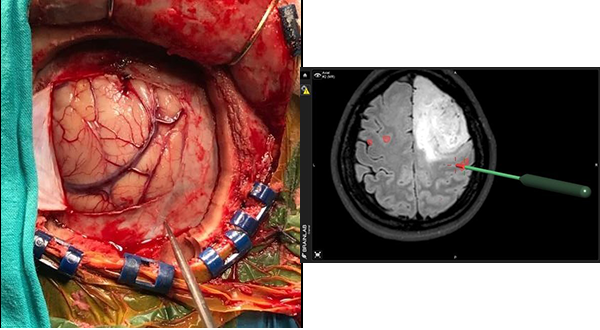

PRUEBAS DIAGNÓSTICAS

Se realizaron mapas de la función motora generados por la Resonancia Magnética Funcional y los mapas intra operatorios generados por la ECD, para validar la utilidad diagnóstica de la RMfm. La integración de estos datos se realizó a través de imágenes obtenidas para localización por neuronavegación.

- Registro y Co registro de Imágenes:

La cirugía se inicia, realizando en la estación de trabajo del navegador Brain Lab Vector Vision II la fusión de imágenes pre quirúrgicas establecidas en el protocolo de neuronavegación antes mencionado por un procedimiento de fusión automática. La secuencia funcional BOLD se fusiona de manera manual, ajustando el tiempo que duran las tareas motoras y los períodos de descanso.

Una vez anestesiado el paciente y fijo a un clamp de Mayfield se realiza el co registro de las imágenes pre quirúrgicas con el paciente a través de registros indirectos de fusión de superficie (Surface Matched) por registro infrarojo, ó por registro directo de imágenes con tomografía computada intraoperatoria (RDII). Esta forma de registro directo elimina los errores de registro indirecto por sistema infrarrojo o electromagnético. Pero su máxima utilidad es permitir la fusión de las imágenes cualquiera fuese la posición quirúrgica de la cabeza ya que la TC intraoperatoria hace visible todo el volumen del cráneo para su correcta fusión con el resto de las imágenes pre quirúrgicas.

Con ayuda de la herramienta de corte se planifica una craneotomía ajustada al criterio de abordaje mínimamente invasivo que exponga los límites del tumor y el área funcional motora indicada por la RMf.

3º Colocación de etiquetas numeradas sobre la superficie cortical, y estimulación espacial cortical directa (ECD)

El tercer paso del monitoreo intraoperatorio es la colocación de stickers numerados que nos permitan reconocer la relación espacial de la corteza quirúrgica con al área de activación de la RMfm. De esta manera se colocaron sobre la superficie cortical distribuyendo en forma aleatoria etiquetas estériles numeradas de 0.5 x 0.5 cm. separadas por una distancia aproximada de 1 cm. Las etiquetas cubrieron toda el área de la craneotomía incluyendo la corteza del tejido funcional registrado en la RMfm (expuesto en el abordaje) y la superficie cortical del tumor. Luego se procedió a la estimulación cortical directa (ECD) con estimulación bipolar con una corriente inicial de 4 mAmp, y si no se obtenían respuestas se incrementó sucesivamente a 8 y 12 mAmp. una frecuencia de 60 Hz y tres pulsos de 0.2 mseg de duración.

La respuesta motora fue evaluada por el neurofisiologo del equipo quirúrgico.